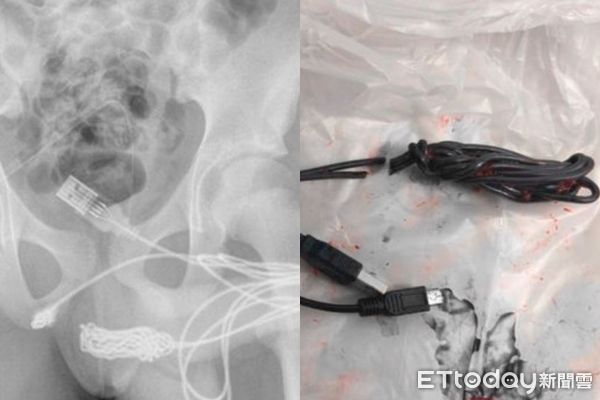

▲醫生發現傳輸線在少年的陰莖內打結。(圖/醫學期刊網站Science Direct)

英國一名15歲的少年疑似因為特殊性癖,竟將USB傳輸線塞進自己的陰莖,呈現兩端插孔在尿道口外、傳輸線卻以打結形式卡在陰莖內的狀態,少年最終因為疼痛不已而前往醫院就醫。醫師雖嘗試取出傳輸線,卻因傳輸線在陰莖內打結而失敗,最後只能切開生殖器與肛門間的部分,從下方接觸電線,才成功取出異物。

醫師第一時間曾試圖將金屬製的空心管從尿道口塞進少年的陰莖,製造空隙後,再將傳輸線拉出來,沒想到卻失敗了。醫護人員發現,傳輸線在少年的生殖器內打結,因此根本無法靠細長的管子疏通並拔出。醫療團隊表示,傳輸線的兩端皆在尿道口外,但中間的部分卻是打結狀態。